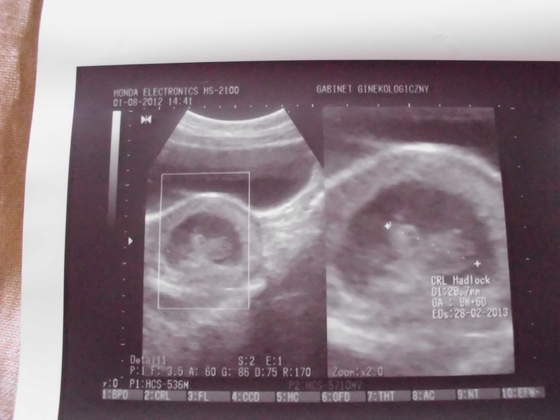

IMG_0453.jpg IMG_0454.jpgIMG_0455.jpgIMG_0456.jpg przedstawiam wszystkim cioteczką z bb moje małe szczęście:)